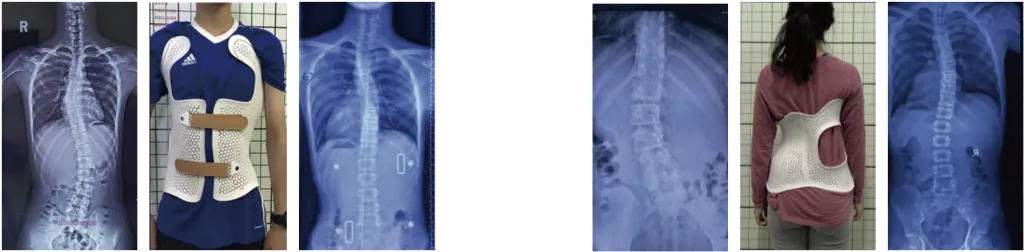

3D-принтер по технологии SLS, специализирующийся на ортопедии

Модель EP-S600 обеспечивает высокую эффективность печати и скорость сканирования, а область построения до 420 x 380 x 600 мм3 полностью отвечает индивидуальным потребностям реабилитационной и медицинской промышленности.

С помощью области построения 420 x 380 x 600 мм принтер может большие ортопедические изделия цельными, что увеличивает их прочность;

Среднее время печати одного ортопедического изделия составляет 11 часов, одна машина может производить 400-450 моделей в год;

В целом, 3D-принтер Eplus3D модели EP-S600 представляет собой передовое решение для ортопедической промышленности. Он обеспечивает высокую эффективность печати, скорость сканирования и удобство использования, а также гарантирует безопасность и надежность процесса. Этот принтер открывает новые возможности для создания индивидуальных ортопедических изделий, способствуя развитию и совершенствованию медицинской промышленности.